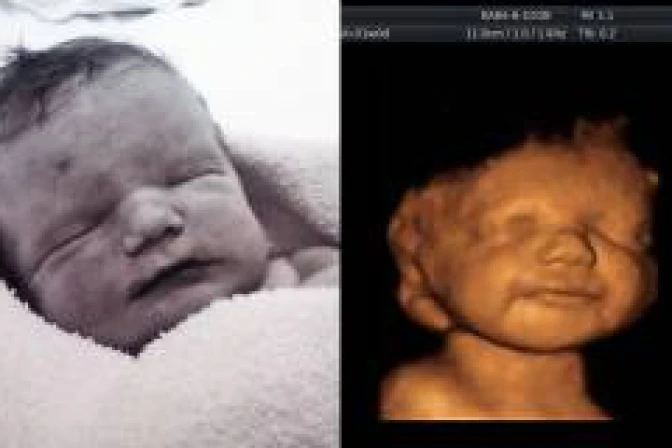

La joven inglesa Katyia Rowe rechazó en varias oportunidades el pedido de aborto por parte de los médicos para su bebé, Lucian Haydes, que iba a nacer con daños cerebrales que le impedirían hablar y caminar y al que le habían diagnosticado una corta vida. Cuando en un ultrasonido (ecografía) 3D lo vio reír y jugar dijo que "yo sabía que no podría terminar con su vida".

Expertos del hospital pediátrico Birmingham confirmaron que el pequeño nunca hablaría ni podría caminar y necesitaría cuidados especiales siempre. Katyia no se amilanó y siguió adelante con el embarazo, haciéndose los ultrasonidos en donde podía ver al niño sonreír, hacer burbujas, patear y mover sus brazos.

"Investigué sobre todos los problemas que tendría para estar preparada en atenderlo, nunca tuve un momento de duda, solo tuve que mirar la ecografía y ver cómo disfruta en el vientre para saber que hacía lo correcto al darle una oportunidad".